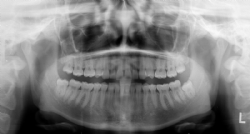

Panorama-Übersichtsaufnahme

Sie zeigt Ober- und Unterkiefer mit allen Zähnen, einschließlich der noch nicht durchgebrochenen, in Entwicklung befindlichen Zähne. Fehlende oder überzählige Zähne, Verlagerungen, Wurzelbildung und Entwicklungsstand sind erkennbar.